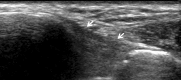

Ankle sonography is one of the most commonly ordered examinations in the field of osteoarticular imaging, and it requires intimate knowledge of the anatomic structures that make up the joint. For practical purposes, the examination can be divided into four compartments, which are analyzed in this pictorial essay: the anterior compartment, which includes the tibialis anterior, extensor hallucis longus, and extensor digitorum longus tendons; the accessory peroneus tertius tendon; and the extensor retinaculum; the medial compartment (tibialis posterior, flexor digitorum longus, and flexor hallucis longus tendons; the flexor retinaculum; the medial collateral-or deltoid-ligament, and the neurovascular bundle); the lateral compartment (peroneus longus, peroneus brevis, and peroneus quartus tendons; superior and inferior peroneal retinacula, lateral collateral ligament); and the posterior compartment (Achilles tendon, plantaris tendon, Kagar's triangle, superficial, and deep retrocalcaneal bursae). Scanning techniques are briefly described to ensure optimal visualization of the various anatomic structures.